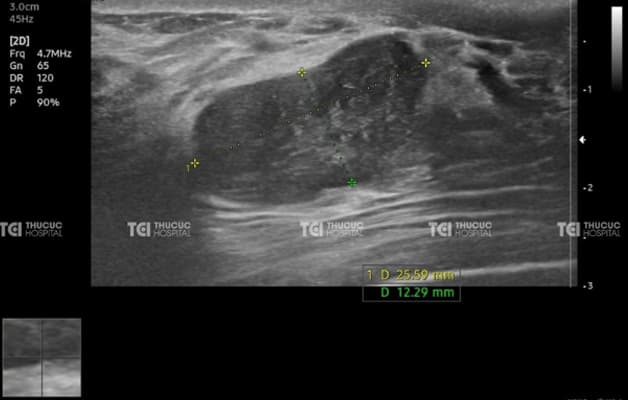

Nhân giảm âm tuyến vú là tổn thương dạng khối, thường ở thể đặc, tồn tại trong tuyến vú. Hầu hết người bệnh mắc nhân giảm âm đều được phát hiện tình cờ qua kiểm tra sức khỏe định kỳ có thực hiện chẩn đoán hình ảnh vú như x-quang hay siêu âm…

Hình ảnh nhân giảm âm tuyến vú được phát hiện qua siêu âm tại Thu Cúc TCI.